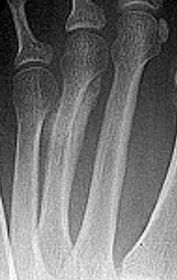

| What disease is this? What indicates this? | Tophaceous gout. Soft tissue swelling surrounding the index finger PIPJ, with associated erosion and bone resorption |